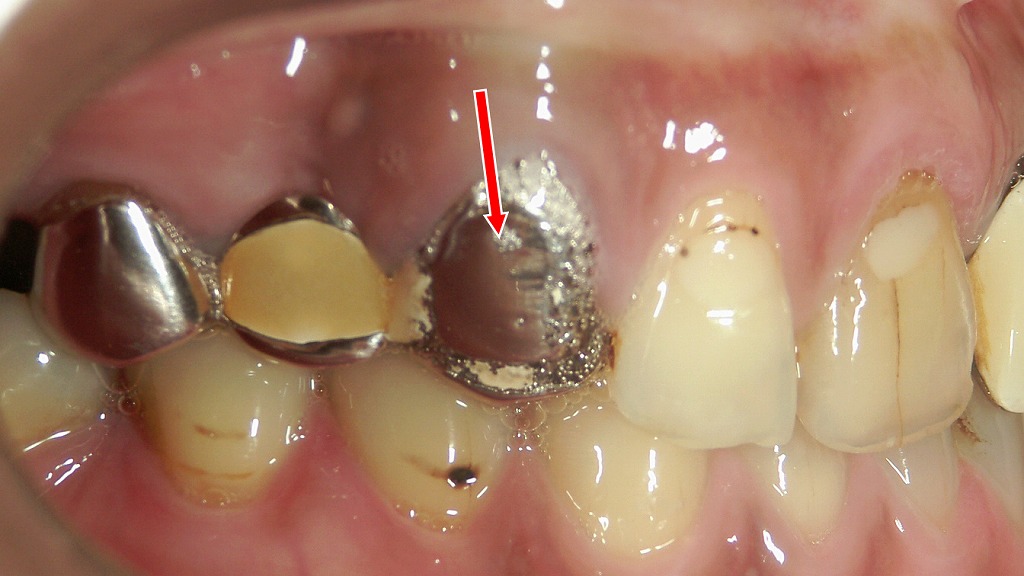

⚠️過重負担による歯根破折を起こした上顎5・6・7番ブリッジ症例

上顎5・6・7番に装着されたブリッジが、長期間にわたり支台歯へ過度の力を集中させた結果、支台歯の一部で歯根破折が生じた症例です。特に奥歯のブリッジは咬合力が強く、支える歯に過重負担がかかりやすいため、経年的に歯根へのダメージが蓄積しやすくなります。破折した歯は保存が難しく、多くの場合は抜歯が必要となり、インプラントなど別の治療法への移行が検討されます。